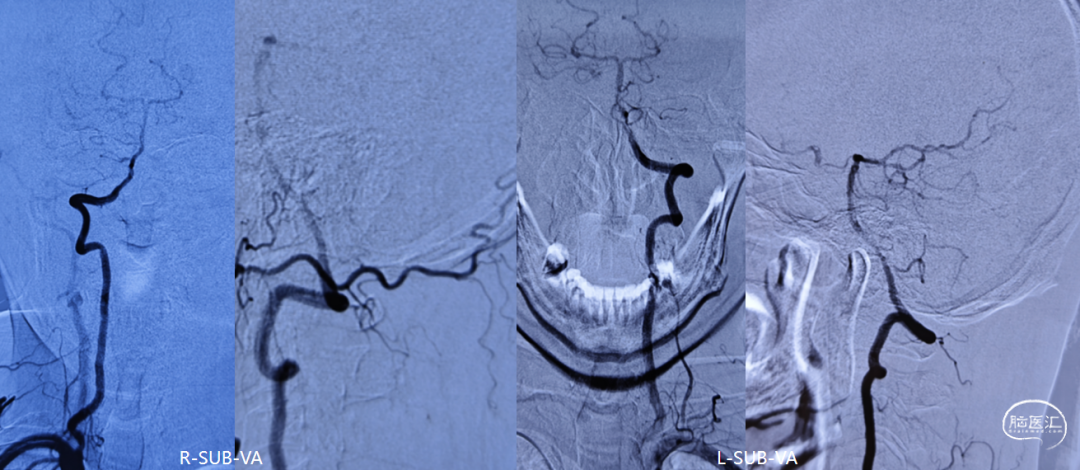

DSA造影(2024.11.07)

右侧颈内动脉起始段闭塞,动脉晚期可见颈动脉颅内段浅淡显影。

前交通动脉开放,右侧大脑中动脉显影良好。

右侧后交通动脉开放,右侧颈动脉颅内段浅淡显影。